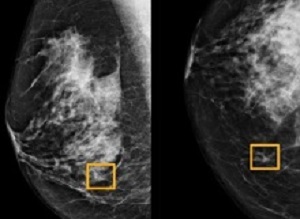

In November, Google Health detailed its mission to “help everybody live their healthiest life.” The division has now published “initial findings” on using artificial intelligence (AI) to improve breast cancer screening. Google notes how “spotting and diagnosing breast cancer early remains a challenge.” Detection today is performed through digital mammography, but reading breast x-ray images is a “difficult task, even for experts, and can often result in both false positives and false negatives.”

The company’s solution involves applying artificial intelligence. Findings that were conducted over the past two years have been published and “show that our AI model spotted breast cancer in de-identified screening mammograms (where identifiable information has been removed) with greater accuracy, fewer false positives, and fewer false negatives than experts.”

What’s notable is how the AI system didn’t have access to patient histories and previous mammograms, like doctors would normally use. The model was trained from de-identified mammograms of 76,000 women in the UK and 15,000 women in the US.